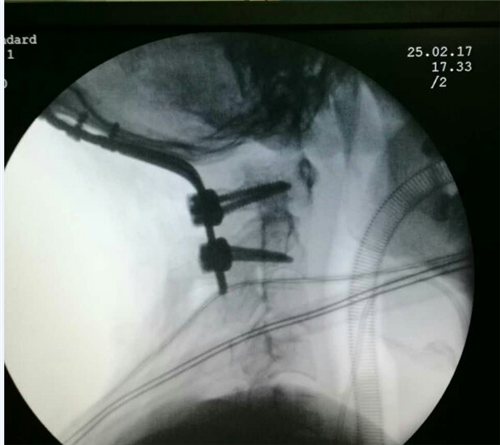

腰椎骨质增生是人的腰椎开始退变发生以及腰椎不稳定的一个表现,本身通常不会引起不适,只有当腰椎骨质增生导致周围组织、神经压迫时,才会引发系列症状表现。…「查看详情」

腰椎骨质增生好发部位以腰三、腰四最为常见。临床上常出现腰椎及腰部软组织酸痛、胀痛、僵硬与疲乏感,甚至弯腰受限。如邻近的神经根受压,可引起相应的症状,出现局部疼痛、发僵、后…「查看详情」